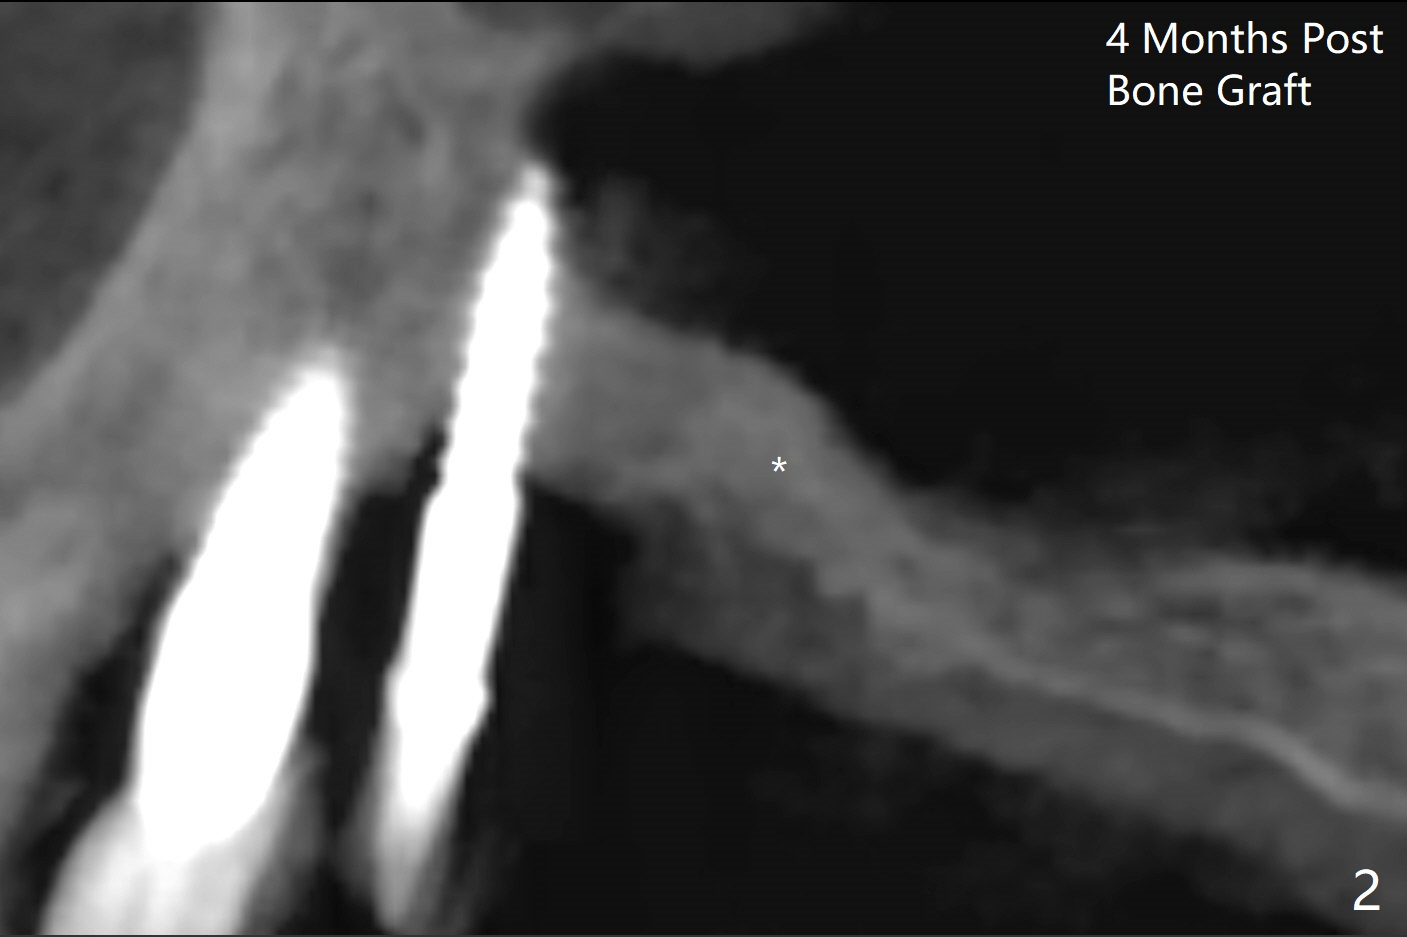

术前清晨复习3号牙窦底,中央是植骨(图一,二:*(皮质骨:密度高,质地可能软)),由于窦底斜坡,术前估计穿孔可能最先发生在远中,术中的确如此(图三:<(使用4毫米钻头后)),放置粘性骨粉(图四),利用导板(图五:G)和4x9毫米报废植体提升(*)。使用4.5毫米钻头,放置半张PRF膜,骨粉,5x7毫米植体以及修复基台,最后在后两者周围放置骨粉(图六,七:*(腭侧一个螺纹暴露)),覆盖1/2PRF膜,缝合,树脂敷料。